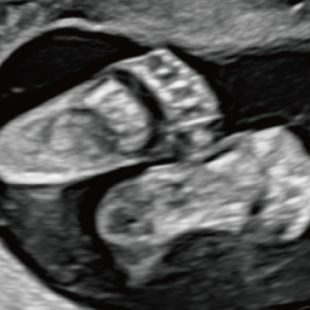

Voluson Expert 22®(GEHealthcare)という産婦人科領域におけるハイエンド超音波診断装置を使用しています。 従来機種と比べ、より高精細な画像描出性能と高度な解析機能を備えており、 胎児の発育や形態をより詳細に観察することが可能です。

妊娠週数により発育段階が異なり、観察しやすい部位や評価できる内容も変化するため、段階的に行うことが重要です。